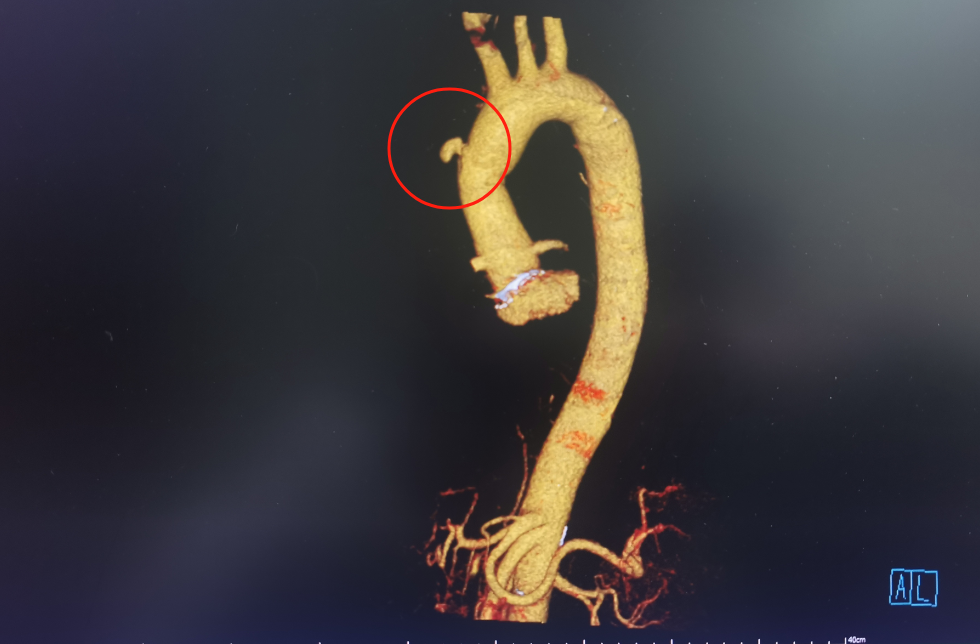

经检查,林先生系升主动脉假性动脉瘤破裂出血,也就是连接心脏最粗的一根动脉血管破裂出血,出血淤积在胸口位置流不出去,才让林先生出现了上述症状。

经过沟通,家属坚持手术,签署手术知情同意书后,介入·血管科为其实施主动脉造影+胸主动脉假性动脉瘤腔内覆膜支架隔绝术。支架随着林先生左侧腹股沟和腋窝两个切口缓慢向心脏移动,但意外还是出现了。由于升主动脉距离心脏近,血管粗、血流冲击大,加之患者胸主动脉破裂部位为人工血管,支架在释放时,被血流冲移位了。为了进一步减小伤害,斯光晏不得不终止手术。

斯光晏教授、胡伟博士、袁罡博士、徐燕能博士从右侧股动脉入路,经鞘送入戈尔40-100mm覆膜支架至升主动脉,精确定位后,缓慢释放支架主体……

缓慢撤出支架输送系统后,造影见主体支架位置固定、展开良好,血流较术前缓慢。随后经胸超声引导下,向瘤腔注射凝血酶,见瘤腔内完全血栓化,血流信号明显减少,置入引流管,见少量淡血性液体流出,假性动脉瘤消失。历时2小时,手术顺利